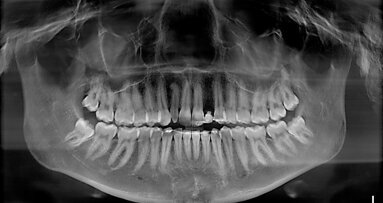

Si è proceduto ad acquisire una scansione CBCT dell’arcata nonché un’impronta digitale, utilizzando un repere su bite personalizzato per permettere il successivo matching delle immagini. Le sezioni CBCT evidenziavano creste di dimensioni ridotte (Fig. 2a) e un’accentuata concavità vestibolare in posizione 22 (Fig. 2b). Il progetto implantare ha previsto l’inserimento di due impianti B1ONE HIGH di dimensioni 3,2 x 12 mm in posizione 12 e 2,7 x 12 mm in posizione 22 (Fig. 3a). Gli impianti selezionati hanno piattaforma SMALL (Ø di 3 mm) e sono caratterizzati da una morfologia di spira (tipo HIGH) realizzata in conformità alle caratteristiche dell’osso24. Contestualmente all’inserimento implantare, la misurazione dell’integrale della curva torque-profondità ha dato conferma di stabilità dell’impianto25, 26. La progettazione implantare è stata quindi condivisa con un laboratorio specializzato (IDI Makers, IDI Evolution) per la realizzazione della corrispondente mascherina chirurgica per chirurgia guidata, con allestimento di piccoli lembi a spessore totale (Fig. 3b).

Fig. 2_Valutazione della disponibilità di spazio mesio-distale e di spessore dell’osso vestibolare; a) visione occlusale in corrispondenza degli elementi 12 e 22; b) immagine panoramica successiva a CBCT con sezione dell’osso vestibolare.